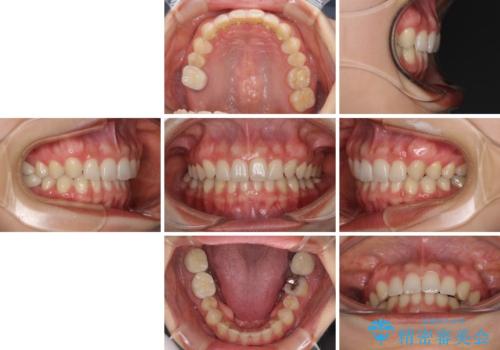

- 前歯の隙間と奥歯の目立つ銀歯を気にして来院された患者様です。

インビザラインにより下顎前歯の隙間を閉じるとともに、奥歯の咬み合わせを改善させることとしました。

矯正治療後には、銀歯のクラウンをセラミッククラウンへ替える補綴治療を行うこととしました。

左右奥歯の咬み合わせを変更させる必要があったため、治療期間は長くなることが予想されました。

1日22時間以上の装着時間をしっかりと守ってくださったので、順調に治療を進めることができました。